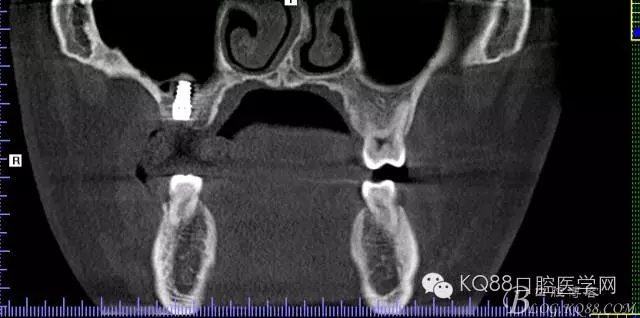

植入后,CBCT

另外一個切面。竇底粘膜完整連續(xù)。可以看到上下咬合的位置關(guān)系。

下面兩張是種植前后的對比片子。

手術(shù)前

手術(shù)后。